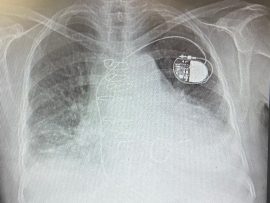

Cardiamed Valve and trans valve pacing wire

Patient with recently inserted Cardiamed valve from Dastavard sina company and trans valve pacing wire [gallery ids="16400,16403"] [playlist ids="16406"] Dr.Sam Zeraatian Nejad Davani, CEO of rockingham medical research ADKWA center..